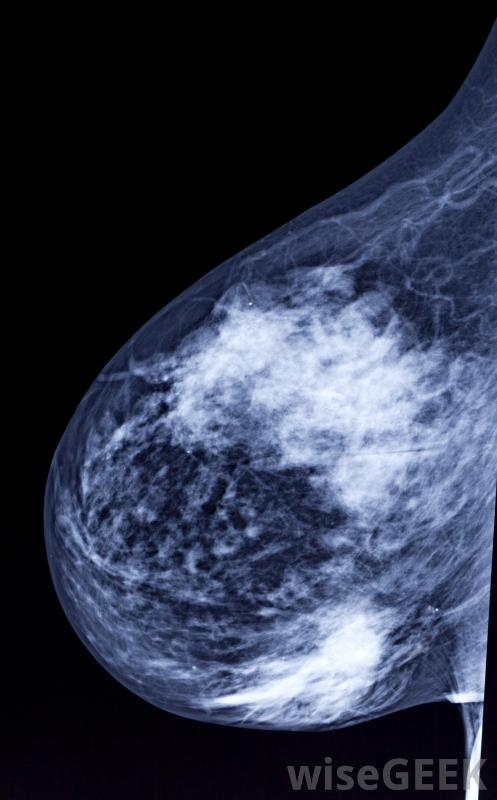

什么是数字乳房X光片(Digital Mammogram)?

数字乳房x光摄影使用传统的x射线方法,但是乳房组织的图像是用电子x光机拍摄的,它以数字格式存储图像。图像在计算机屏幕上显示,然后放射科医生可以调整对比度,增强或放大x光片以显示检测结果。传统的乳房x光片在胶片上生成图像,放射科医生和医生通过将图像置于光源上进行检查由于胶片曝光不足或曝光过多,数字乳房X光片不再需要重复扫描。数字乳房X光片需要更少的时间来记录图像,以检查是否存在异常乳房组织,从而减少与手术相关的疼痛。检查要求将乳房放在一个平坦的表面上,在进行x光检查时,有一个装置压迫乳房。乳房的组织需要展开,以允许机器观察所有的组织,并防止组织堵塞异常在拍摄图像时,女性必须保持非常安静,避免呼吸,以防止x射线散射或无法读取的扫描乳房组织很少有研究证实数字乳房X光摄影的好处,但是一些科学家和医生已经展示了使用这项技术的有希望的结果,由于在乳腺组织成像过程中由于运动而导致扫描不可读,重复的乳房X光片减少了。数字乳房X光片允许放射科医生通过编辑技术改进测试图像,从而产生更清晰的结果,更容易检测肿块或肿瘤样结构。这种技术由于胶片曝光不足或曝光过多,也不再需要重复扫描。对于一些办公室和患者来说,测试成本是一个问题,但由于数字乳房X光片是数字化存储的,它降低了员工和存储空间的开销胶片。数字化筛查的完成速度要快得多,让放射科医生可以在一天内完成更多的乳房X光片检查。在较短的手术过程中,女性受到的辐射较少,这可能有助于缓解一些患者的安全顾虑。数字成像技术的进步可能会给筛查中心带来未来的好处,并且为病人提供更准确的结果。建议50岁以上的妇女每两年进行一次乳房X光检查。乳房X光检查可以发现可能是乳腺癌征兆的肿瘤或肿块。定期检查建议医生将之前的扫描结果与当前图像进行比较,以确定是否有变化或增长。